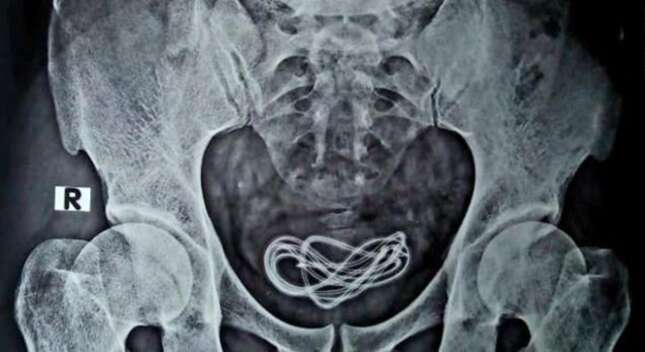

La rocambolesca historia tuvo lugar el pasado mes de mayo en el noroeste de India. Un hombre llega al hospital…